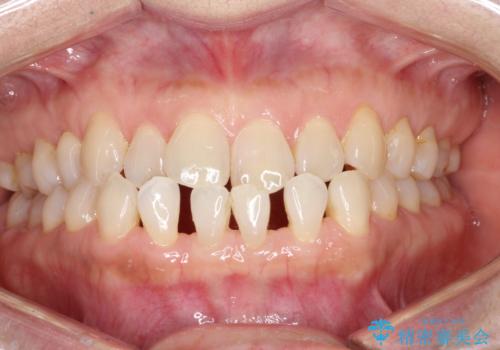

軽度の前歯のガタガタをインビザラインでの目立たない矯正

- 前歯のガタガタを主訴に来院されました。

軽度であったため、枚数制限のあるタイプのインビザラインのプランで治療することとしました。

軽度のガタガタを目立たずに手軽に矯正できるのもマウスピース矯正の魅力といえます。